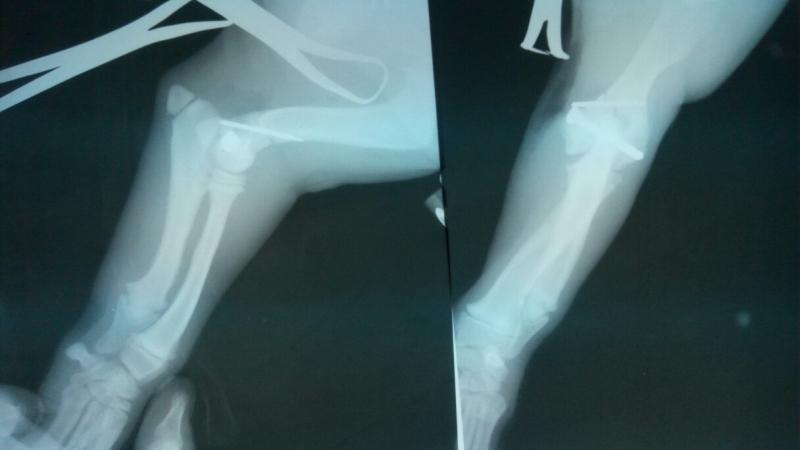

Постановкой диагноза должен заниматься квалифицированный специалист, который оценит рентгеновские снимки, сделанные после травмы в двух проекциях.

Перелом плеча проявляется различными симптомами, а лечение определяется на основе окончательного диагноза, установленного врачом.